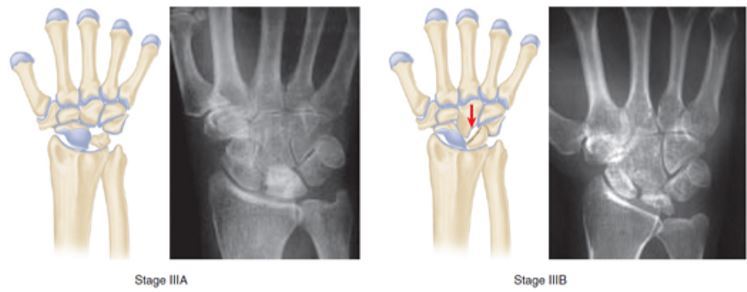

Como é o estágio III de Lichtman

IIIA: COLAPSO do semilunar mas altura carpal mantida

No perfil semilunar tem Distância AP alargada

IIIB: Capitato migra proximalmente

******Escafoide em Flexão******

Diminuição da altura carpal

DISI

******Ângulo RadioEscafoide > 60º******